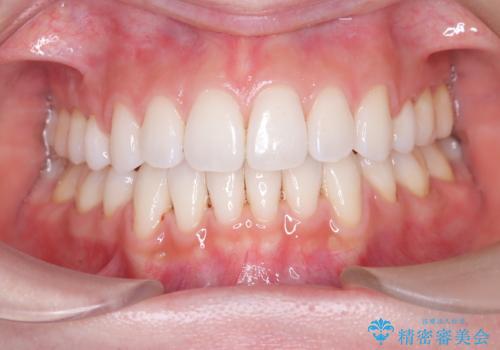

上下左右の小臼歯を抜歯後、ワイヤー矯正装置を装着し、全体のバランスを見ながら歯を移動させていきました。特に前歯の後方移動では、抜歯スペースを活かして口元を内側に下げることに重点を置きました。また、八重歯も時間をかけて丁寧に整列させ、左右の正中(真ん中の位置)もぴったりと揃えることができました。

治療期間は約2年で、歯並びだけでなく横顔の印象も大きく改善されました。治療後には「口元がすっきりして笑顔に自信が持てるようになった」とのお声をいただきました。現在は後戻りを防ぐため、保定装置(リテーナー)を使用しながら経過観察中です。ワイヤー矯正は審美性と機能性を両立できる有効な選択肢の一つです。